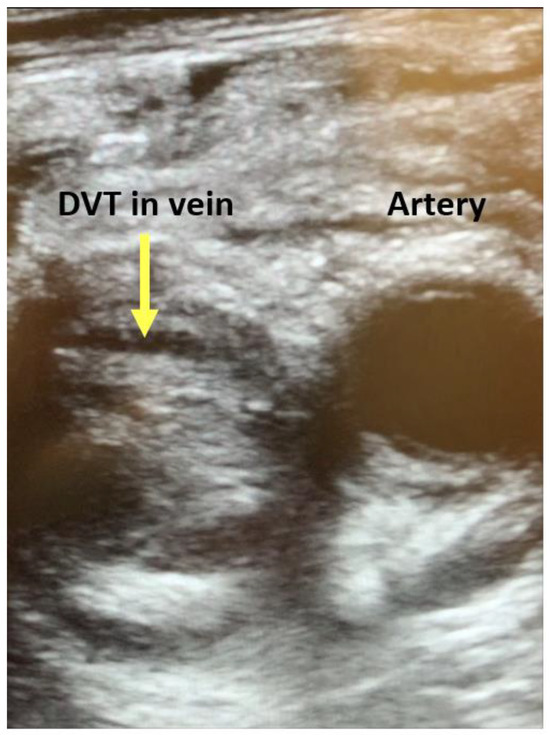

- Barrosse-Antle, M.E.; Patel, K.H.; Kramer, J.A.; Baston, C.M. Point-of-Care ultrasound for bedside diagnosis of lower extremity DVT. Chest 2021, 160, 1853–1863. [Google Scholar] [CrossRef]